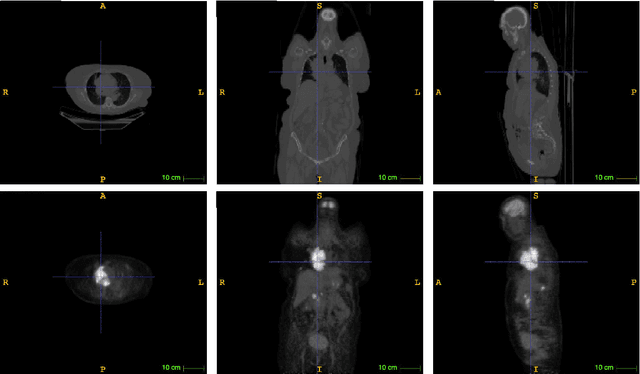

Abstract:Lymphoma detection and segmentation from whole-body Positron Emission Tomography/Computed Tomography (PET/CT) volumes are crucial for surgical indication and radiotherapy. Designing automatic segmentation methods capable of effectively exploiting the information from PET and CT as well as resolving their uncertainty remain a challenge. In this paper, we propose an lymphoma segmentation model using an UNet with an evidential PET/CT fusion layer. Single-modality volumes are trained separately to get initial segmentation maps and an evidential fusion layer is proposed to fuse the two pieces of evidence using Dempster-Shafer theory (DST). Moreover, a multi-task loss function is proposed: in addition to the use of the Dice loss for PET and CT segmentation, a loss function based on the concordance between the two segmentation is added to constrain the final segmentation. We evaluate our proposal on a database of polycentric PET/CT volumes of patients treated for lymphoma, delineated by the experts. Our method get accurate segmentation results with Dice score of 0.726, without any user interaction. Quantitative results show that our method is superior to the state-of-the-art methods.

Abstract:PET and CT are two modalities widely used in medical image analysis. Accurately detecting and segmenting lymphomas from these two imaging modalities are critical tasks for cancer staging and radiotherapy planning. However, this task is still challenging due to the complexity of PET/CT images, and the computation cost to process 3D data. In this paper, a segmentation method based on belief functions is proposed to segment lymphomas in 3D PET/CT images. The architecture is composed of a feature extraction module and an evidential segmentation (ES) module. The ES module outputs not only segmentation results (binary maps indicating the presence or absence of lymphoma in each voxel) but also uncertainty maps quantifying the classification uncertainty. The whole model is optimized by minimizing Dice and uncertainty loss functions to increase segmentation accuracy. The method was evaluated on a database of 173 patients with diffuse large b-cell lymphoma. Quantitative and qualitative results show that our method outperforms the state-of-the-art methods.